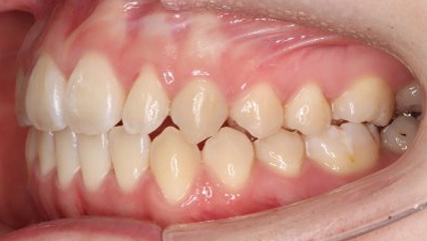

上顎前突といわれ、上顎の前歯が唇側に出ている状態を言います。

前歯が出ることで見た目の問題もありますが、口を閉じることができない、口呼吸をしてしまう、外傷などのリスクがあります。

日本人に叢生の次に多い不正咬合と言われており、自然に治ることはありません。また上の前歯が出ている事だけが気になるかもしれませんが、多くの場合、上顎の奥歯の位置に問題があることが多く、部分矯正でなく根本的な治療をした方がいい場合が殆どです。

口を閉じることができないことで、鼻呼吸でなく口呼吸をしてしまい、結果、成長期の場合顎の骨の成長を邪魔してしまうとも言われております。その他、口呼吸はアトピーなどを含むアレルギー症状の悪化、風邪を含むウイルス性の感染症にかかりやすいなどのリスクも増大してしまいます。

歯並びだけでなく全身への影響も多い為、早期の治療をおすすめ致します。